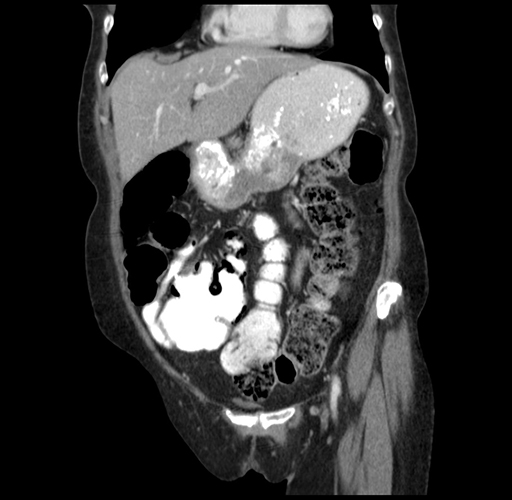

Pre-Chemo: Coronal Venous

Coronal Venous